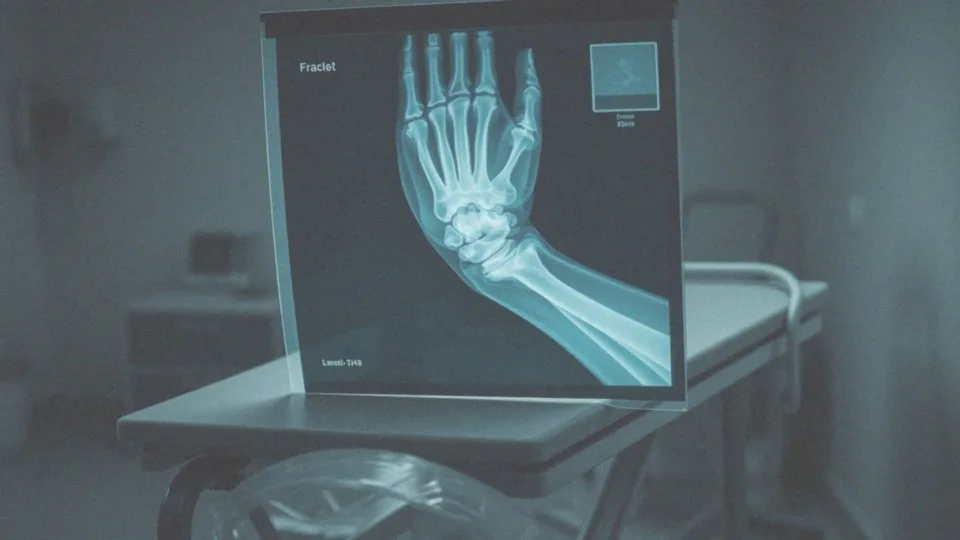

W diagnostyce często wykorzystuje się badania obrazowe, które umożliwiają ocenę stanu kości i nerwów. Odpowiednio dobrane leczenie, które może obejmować także fizjoterapię i regularny monitoring procesu gojenia, w znacznym stopniu poprawia komfort pacjenta oraz przywraca pełną funkcjonalność kończyny.

Szybkie postawienie diagnozy, w tym wykonanie badań obrazowych, jest niezwykle ważne, aby dokładnie ocenić stan nerwów oraz kości, co wpływa na skuteczność leczenia. Rehabilitacja po złamaniu nadgarstka ma również kluczowe znaczenie w łagodzeniu tych dolegliwości.

Badanie rentgenowskie (RTG) jest niezwykle istotne, ponieważ pozwala na analizę zrostu kostnego oraz identyfikację ewentualnych zmian w strukturze kości, co jest niezbędne w przypadku złamań. W bardziej skomplikowanych sytuacjach wykorzystuje się tomografię komputerową (TK), która umożliwia dokładną ocenę kostnych elementów nadgarstka. Z kolei elektromiografia (EMG) oraz elektroneurografia (ENG) dostarczają informacji o funkcjonowaniu nerwów i mogą ujawnić potencjalne uszkodzenia prowadzące do drętwienia.